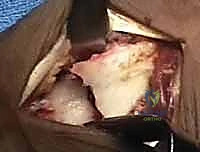

يقوم الدكتور هطيف بعمل 2 إلى 3 ثقوب دقيقة جداً (Portals) في ظهر الرسغ. يتم إدخال الكاميرا من ثقب، وأدوات العمل الجراحية الدقيقة من الثقوب الأخرى.

الخطوة الرابعة: رد الكسر تحت الرؤية المباشرة

باستخدام أدوات دقيقة، يتم تحريك القطع العظمية المكسورة وإعادتها إلى مكانها الطبيعي. يراقب الجراح العملية عبر شاشة المنظار ليتأكد من أن السطح المفصلي أصبح مستوياً تماماً بنسبة 100%.

الخطوة الخامسة: التثبيت الداخلي

بمجرد استعادة الشكل التشريحي، يتم تثبيت العظام. قد يتم استخدام أسلاك كيرشنر (K-wires)، مسامير دقيقة، أو شريحة معدنية داعمة (Volar Plate) توضع من خلال شق صغير منفصل لضمان ثبات الكسر التام. يتم أيضاً خياطة أي تمزق في الأربطة إن وجد.